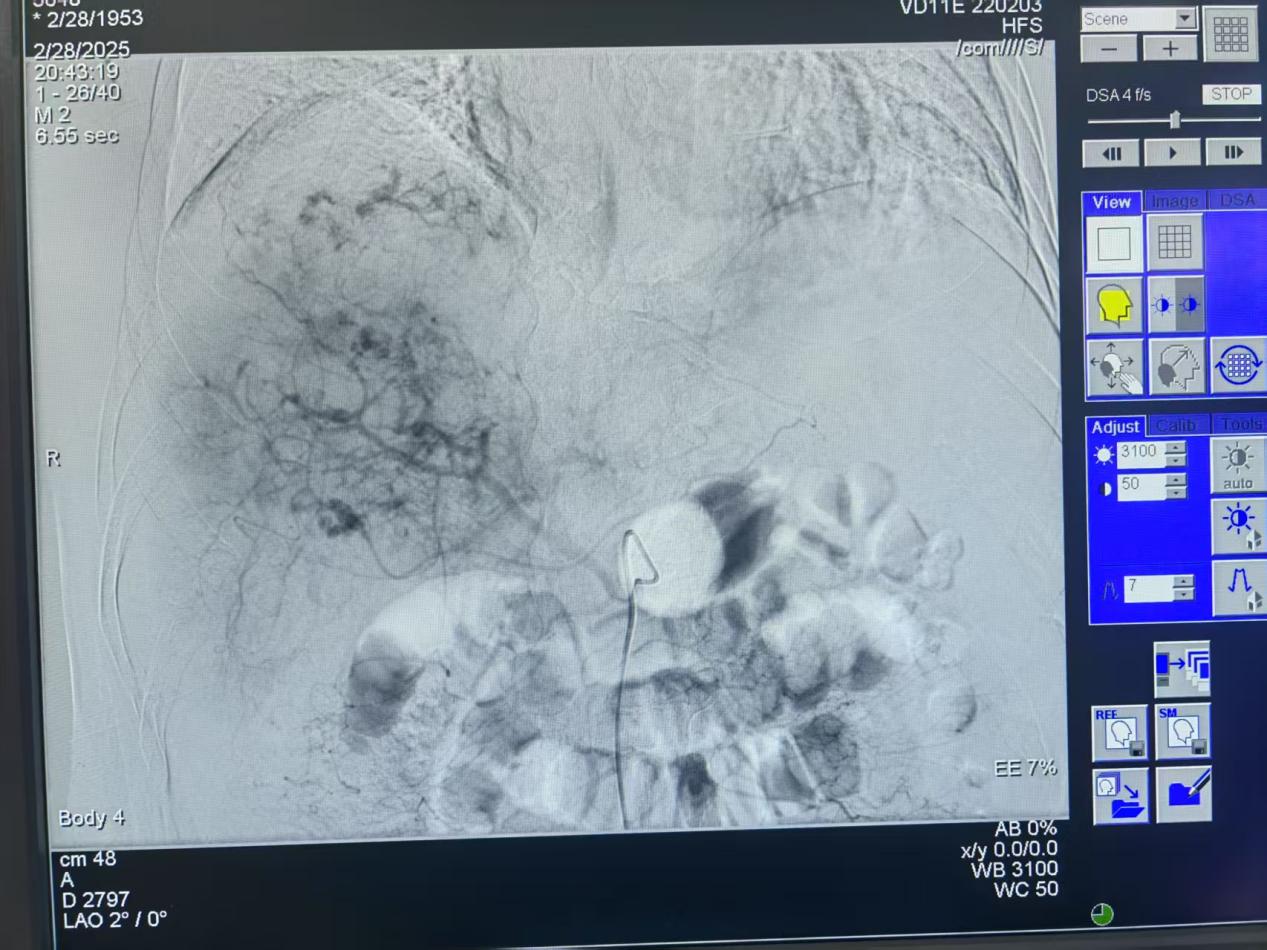

術(shù)前患者肝臟血管造影圖片

圖片8.jpg